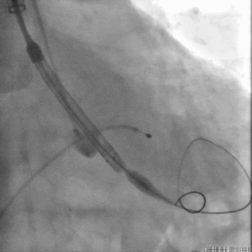

跨瓣DSA

根部造影

瓣膜释放DSA

最后一枪造影